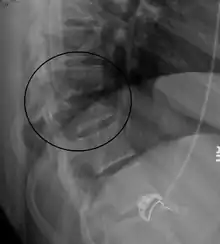

Chance fracture

A Chance fracture is a type of vertebral fracture that results from excessive flexion of the spine.[8] Symptoms may include abdominal bruising (seat belt sign), or less commonly paralysis of the legs.[4][9] In around half of cases there is an associated abdominal injury such as a splenic rupture, small bowel injury, pancreatic injury, or mesenteric tear.[3][5] Injury to the bowel may not be apparent in the first day.[10]

| A Chance fracture of T10 and fracture of T9 due to a seatbelt during an MVC. | |

The cause is classically a head-on motor vehicle collision in which the affected person is wearing only a lap belt.[2] Being hit in the abdomen with an object like a tree or a fall may also result in this fracture pattern.[11][9] It often involves disruption of all three columns of the vertebral body (anterior, middle, and posterior).[7][6] The most common area affected is the lower thoracic and upper lumbar spine.[6] A CT scan is recommended as part of the diagnostic work-up to detect any potential abdominal injuries.[5] The fracture is often unstable.[1]

On plain X-ray, a Chance fracture may be suspected if two spinous processes are excessively far apart.[9]